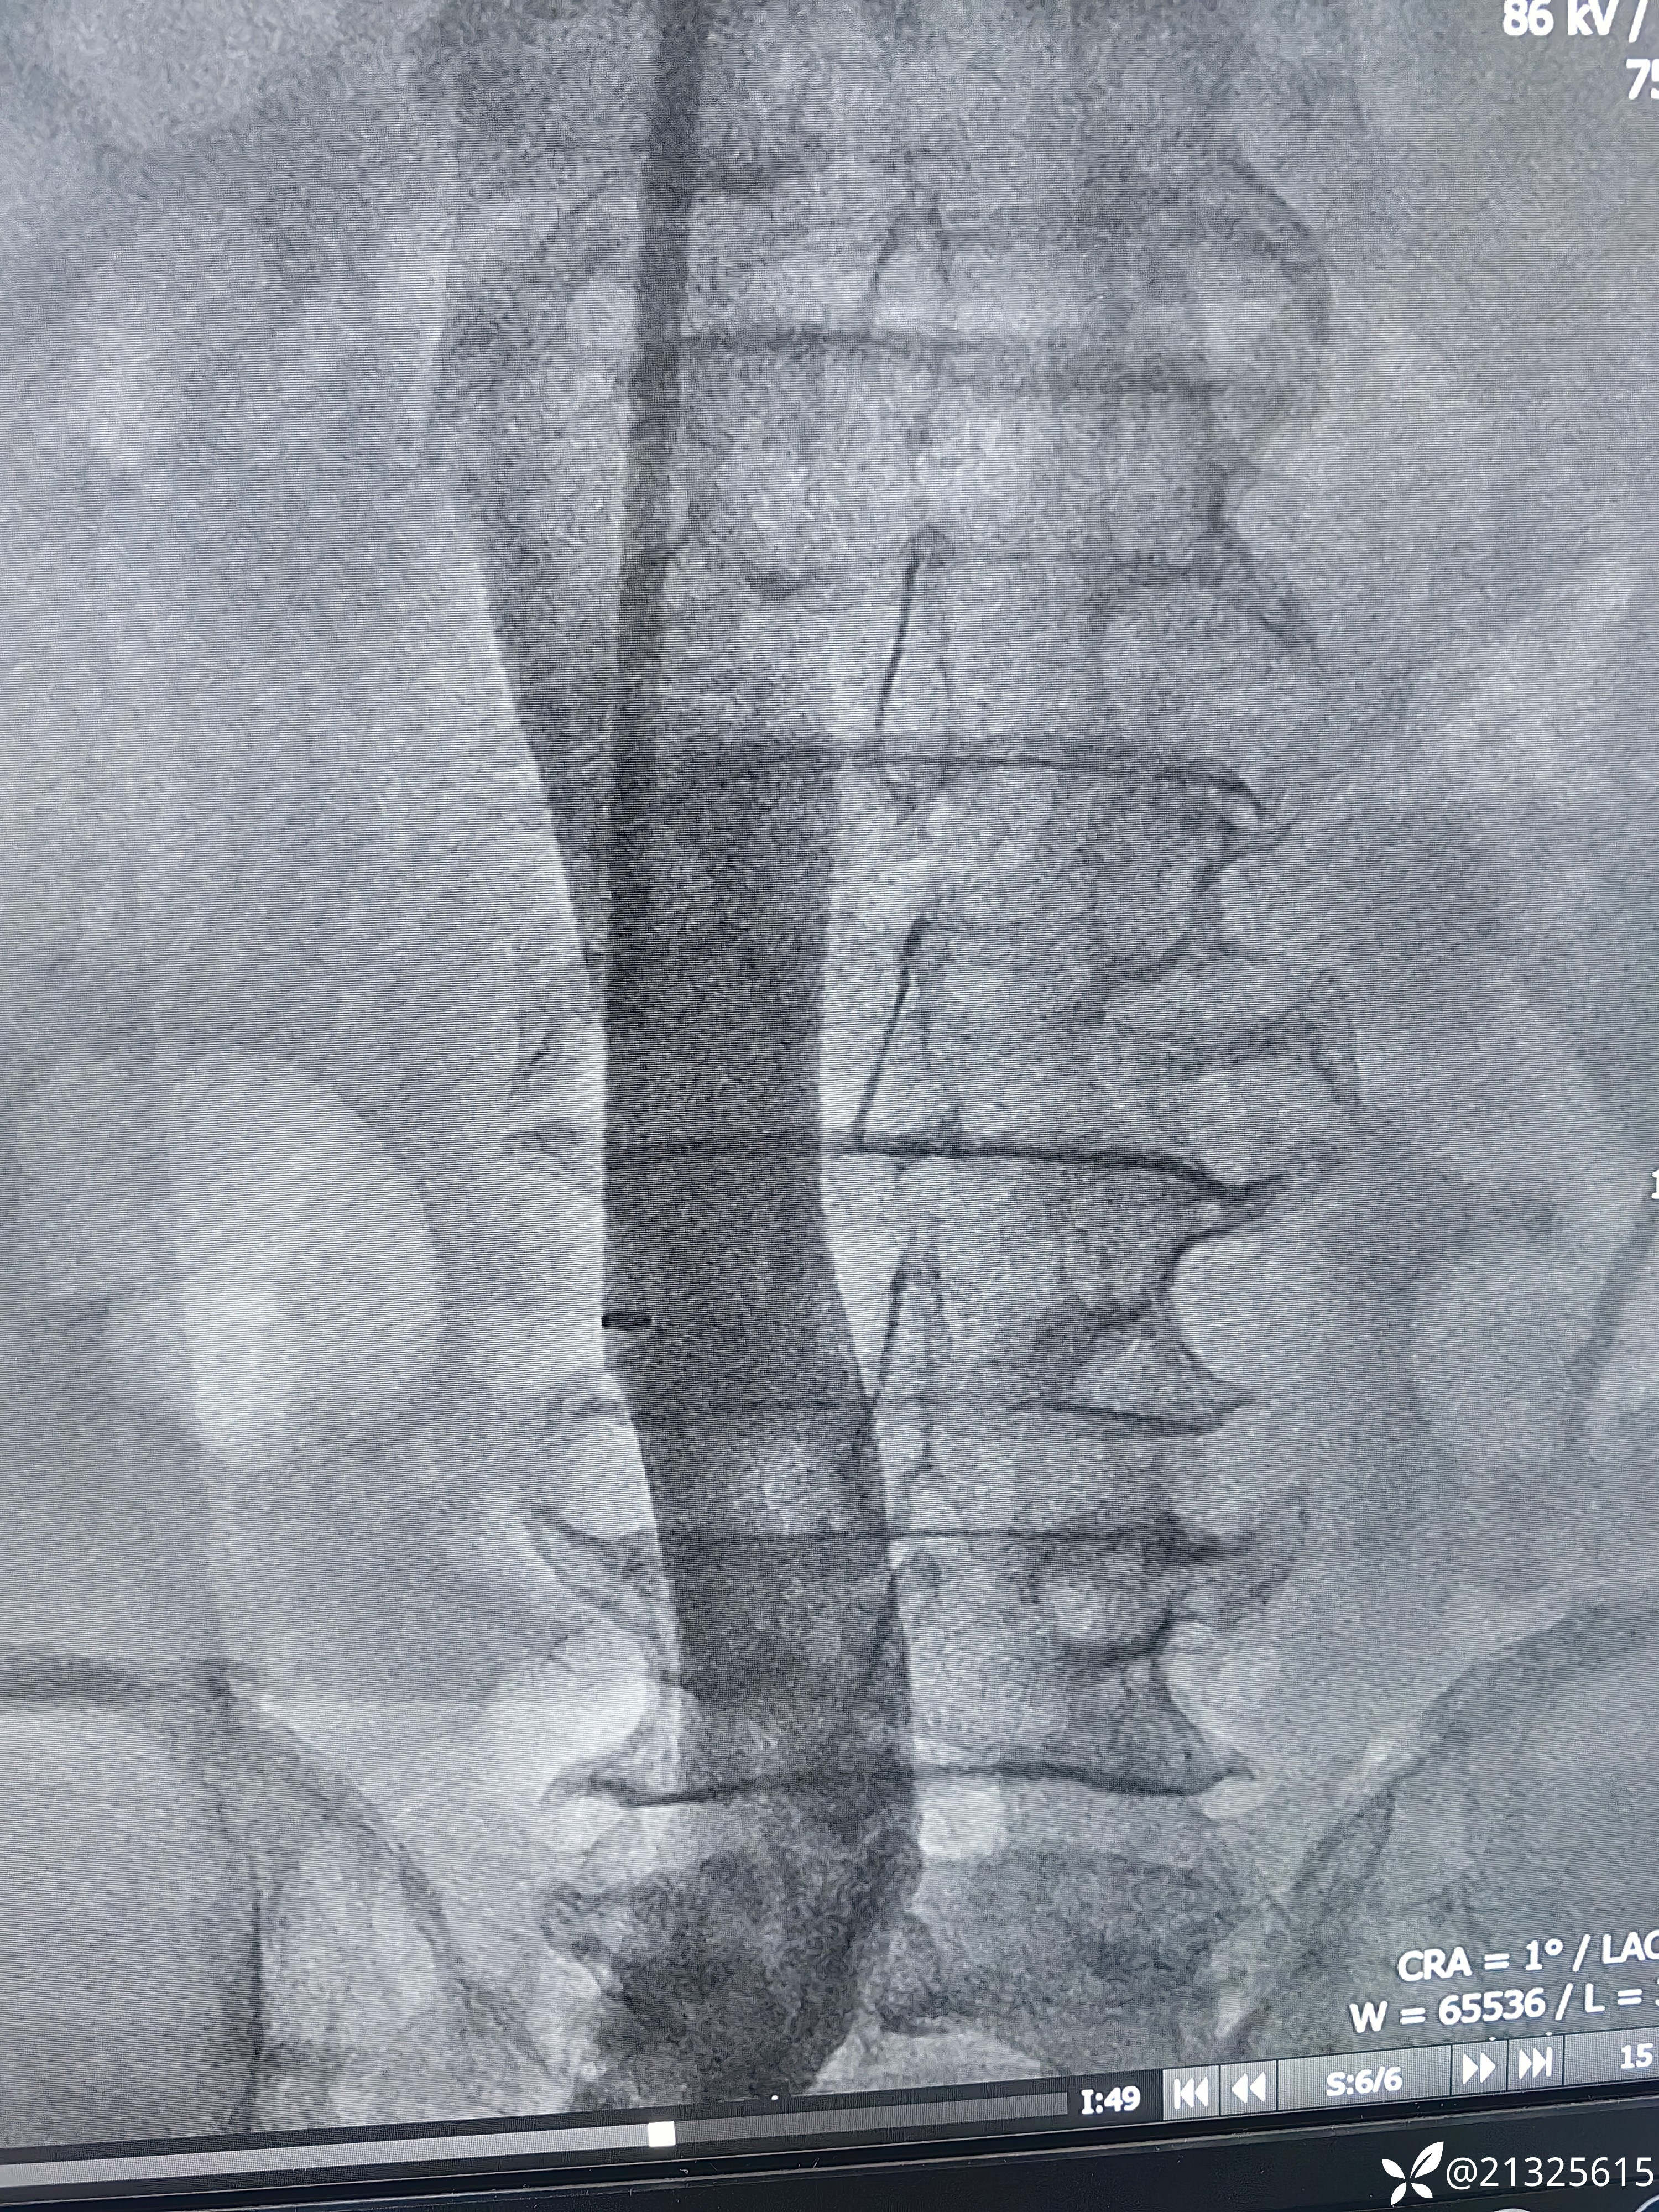

完善术前检查后,患者平卧位,心电监护、吸氧。右侧颈部消毒铺巾,2%卡因局麻后穿刺颈内静脉,植入造影导管。造影示滤器位置正常,无充盈缺损。

送入取滤器套件,以环状抓捕器套住滤器顶端小钩,

推入外壳将其纳入鞘管取出

。再次造影无外溢,